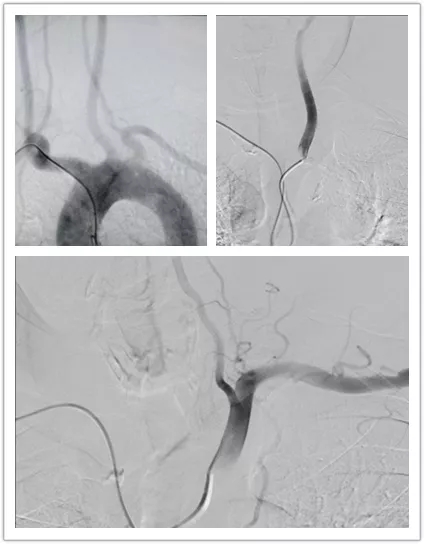

7月30日上午10时10分,陈伯进入介入室准备行造影术。15分后,医生为陈伯右侧桡动脉穿刺并置鞘成功。随后,介入团队通过使用泥鳅导丝、猪尾巴管和西蒙管分别对主动脉弓、左侧颈总动脉、左侧锁骨下动脉、右侧颈总动脉、右侧锁骨下动脉进行造影,术程顺利。10时40分,陈伯的手术顺利完成。由于穿刺点位于手部,陈伯术后也可自由活动,无需卧床制动,其日常生活受手术影响不大。